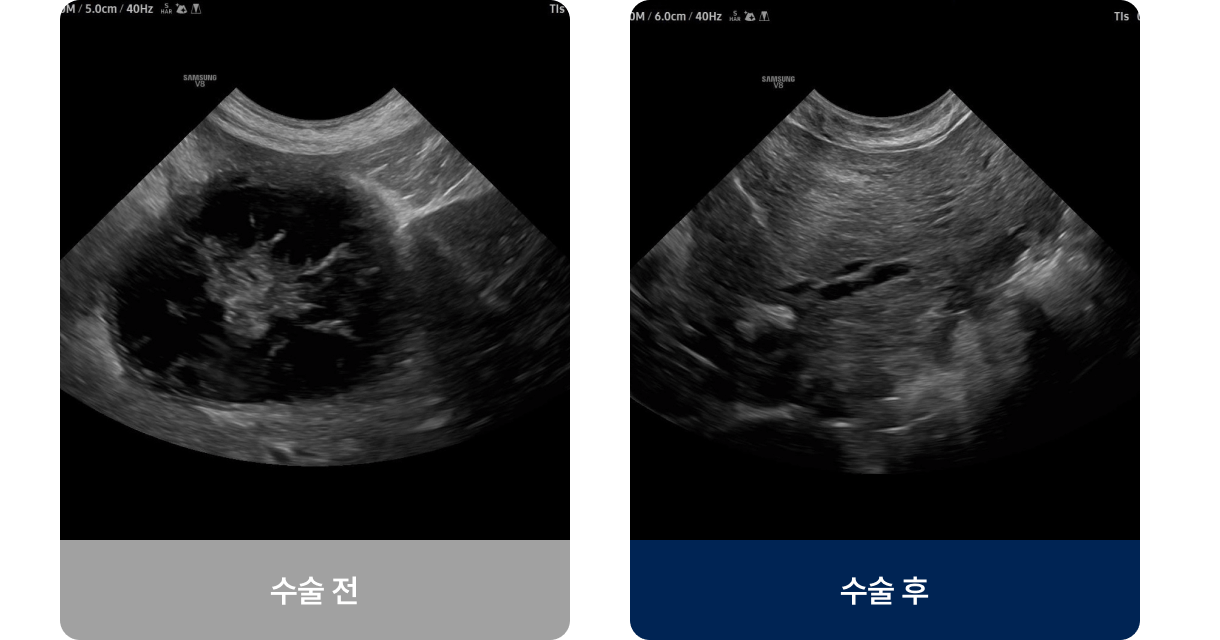

간에서 만든 담즙을 담아주는 작은 주머니인 담낭 안에 끈적한 점액이 과도하게 축적되는 상태로, 담즙이 제대로 배출되지 못하고 담낭 벽이 늘어나거나 터질 위험이 있습니다. 중년 이상의 강아지에게 발병률이 높으며, 식욕 저하·구토·황달 증상을 보입니다.

간에서 만든 담즙을 담아주는 작은 주머니인 담낭 안에 끈적한 점액이 과도하게 축적되는 상태로, 담즙이 제대로 배출되지 못하고 담낭 벽이 늘어나거나 터질 위험이 있습니다. 중년 이상의 강아지에게 발병률이 높으며, 식욕 저하·구토· 황달 증상을 보입니다.

외과적 치료법(수술적 치료)

담낭절제술

• 개복 또는 복강경을 통해 담낭 전체를 제거

• 담즙은 간에서 직접 장으로 흘러가므로, 담낭 제거 후에도 소화 기능

유지 가능

• 수술 전후 혈액검사·초음파·CT로 간·담관 상태 확인

• 수술 후 입원 모니터링(24~48시간), 저지방 식이 + 약물 보조